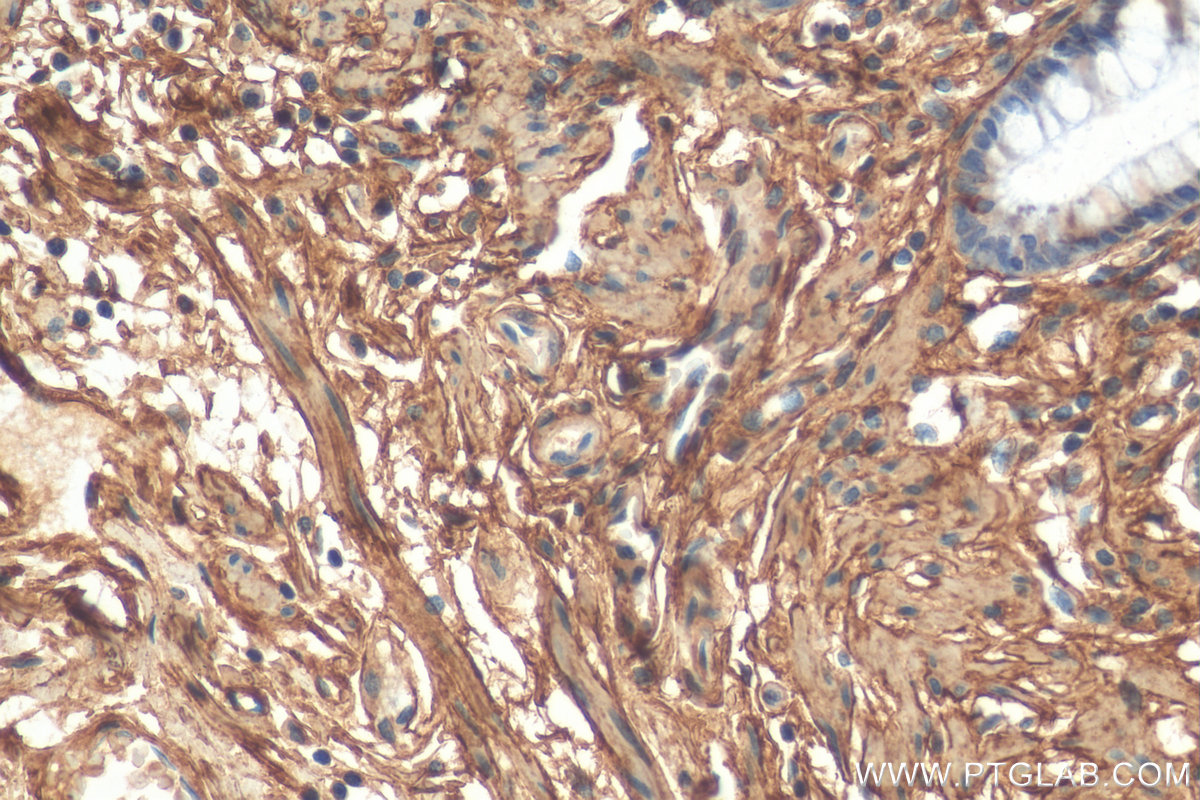

| Positive IHC detected in | human colon tissue, human liver tissue, mouse liver tissue, human heart tissue, human hepatocirrhosis tissue, human kidney tissue, human placenta tissue, human testis tissue, human spleen tissue, human lung tissue, human ovary tissue, human skin cancer tissue Note: suggested antigen retrieval with TE buffer pH 9.0; (*) Alternatively, antigen retrieval may be performed with citrate buffer pH 6.0 |

17023-1-AP targets COL6A1 in WB, IHC, IF, IF-P, IP, ELISA applications and shows reactivity with human, mouse, rat samples.

Type VI Collagen is a major structural component of microfibrils. Type VI Collagen was found to be present throughout the connective tissue and in the extracellular matrix of cultured fibroblasts (PMID: 6723253). It is a heterotrimer composed of three different chains: alpha-1(VI), alpha-2(VI), and alpha-3(VI) or alpha-5(VI) or alpha-6(VI). The alpha-1(VI) chain is encoded by COL6A1 gene. Mutations in this gene result in Bethlem myopathy and Ullrich congenital muscular dystrophy.